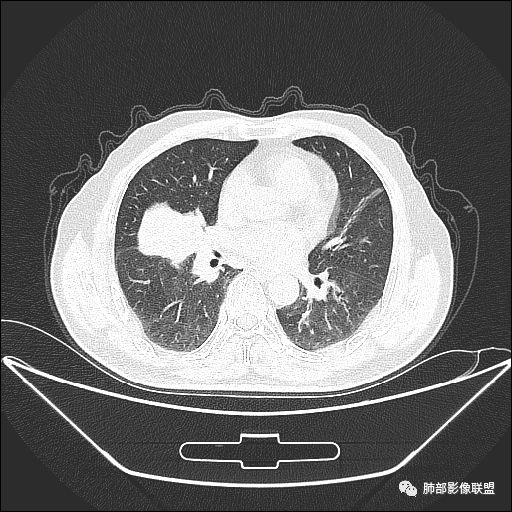

入院CT

老年男性,亚急性病程,咳嗽咳痰。右肺中叶团片影,外朝内分布,大部分边界清楚平直,内侧支气管进入,团片影见低密度坏死区,强化明显,延迟强化,血管破坏不明显,符合爬行征5个特点:

1.肺外周生长。

2.外侧部分体积大于内侧。

3.病变最大径与肺的纵轴及水平面任何一条轴线不平行。

4.病变内侧支气管通畅。

5.病变区域肺容积无缩小。

空气储留,支气管炎

管辖的支气管是壁增厚,狭窄的

它不是只有一支支气管有问题,而是多支

这个是上叶支气管,而且一般慢性炎症更容易空气储留,因为是缓慢的才会气体易进难出。

主病灶在中叶,但是左肺舌段叶有条索影,陈旧病变。蓝色箭头支气管受压,是淋巴结肿大

主病灶在中叶,但是还有结节状病变在下叶

是这样长过去的吗?

叶间裂推移方向

虽然是一个大的病灶,但是周围是比较散

下面我们看看支气管都在吗?

内侧段是通畅但是受压的

外侧段一开始狭窄

但是远端通畅,所以我认为支气管都没有堵塞,不太可能是鳞癌

边缘还有多发小灶

淋巴结肿大,钙化。

但是钙化,密度高,没有融合,平扫没有坏死

病灶明显平直,中央是粘液栓,低密度,分界清楚

综上,考虑炎症,结核。

吴婧老师和南边老师都对该病例进行了深入分析。从支气管管壁的增厚,支气管狭窄后扩张,支气管粘液栓,病灶形态,到病灶不均匀强化及坏死彻底,到周边病灶及肺组织空气的潴留,加之纵隔内淋巴结肿大伴钙化等等,都支持慢性炎性病灶,尤其是结核。

现在小编来增加一个炎性另一个征象,是我们王兆宇老师原创的----就是墨西哥仙人掌征。

墨西哥仙人掌征---结核        影像上结核灶,粗大的均匀枝干,推测是支气管囊状扩张引起的,在非支气管区,形成圆形坏死囊群;如果这些坏死比较稀薄,又遇到扩张支气管,就会形成粗大的“墨西哥仙人掌”。结核引起的支气管近端炎症纤维化,可以造成支气管阻塞,从而将干酪样坏死物封堵在管腔内。仙人掌主干内部应该是干酪为主,稀薄的,具有流动性,时间久了会出现钙化。

结核坏死与鳞癌鉴别有一点是结核坏死没有方向性,鳞癌有。鳞癌靠近支气管近端部分,血供容易维持,不易坏死,所以坏死靠外侧。而结核干酪样坏死,把一定体积的流动性坏死物,包裹起来,什么形状最省料?坏死物包裹,表面积最省的自然是圆球形,而遇到支气管,坏死物一多,就把支气管撑大了。包裹物是就地取材,扩张的支气管就成了包裹结构。